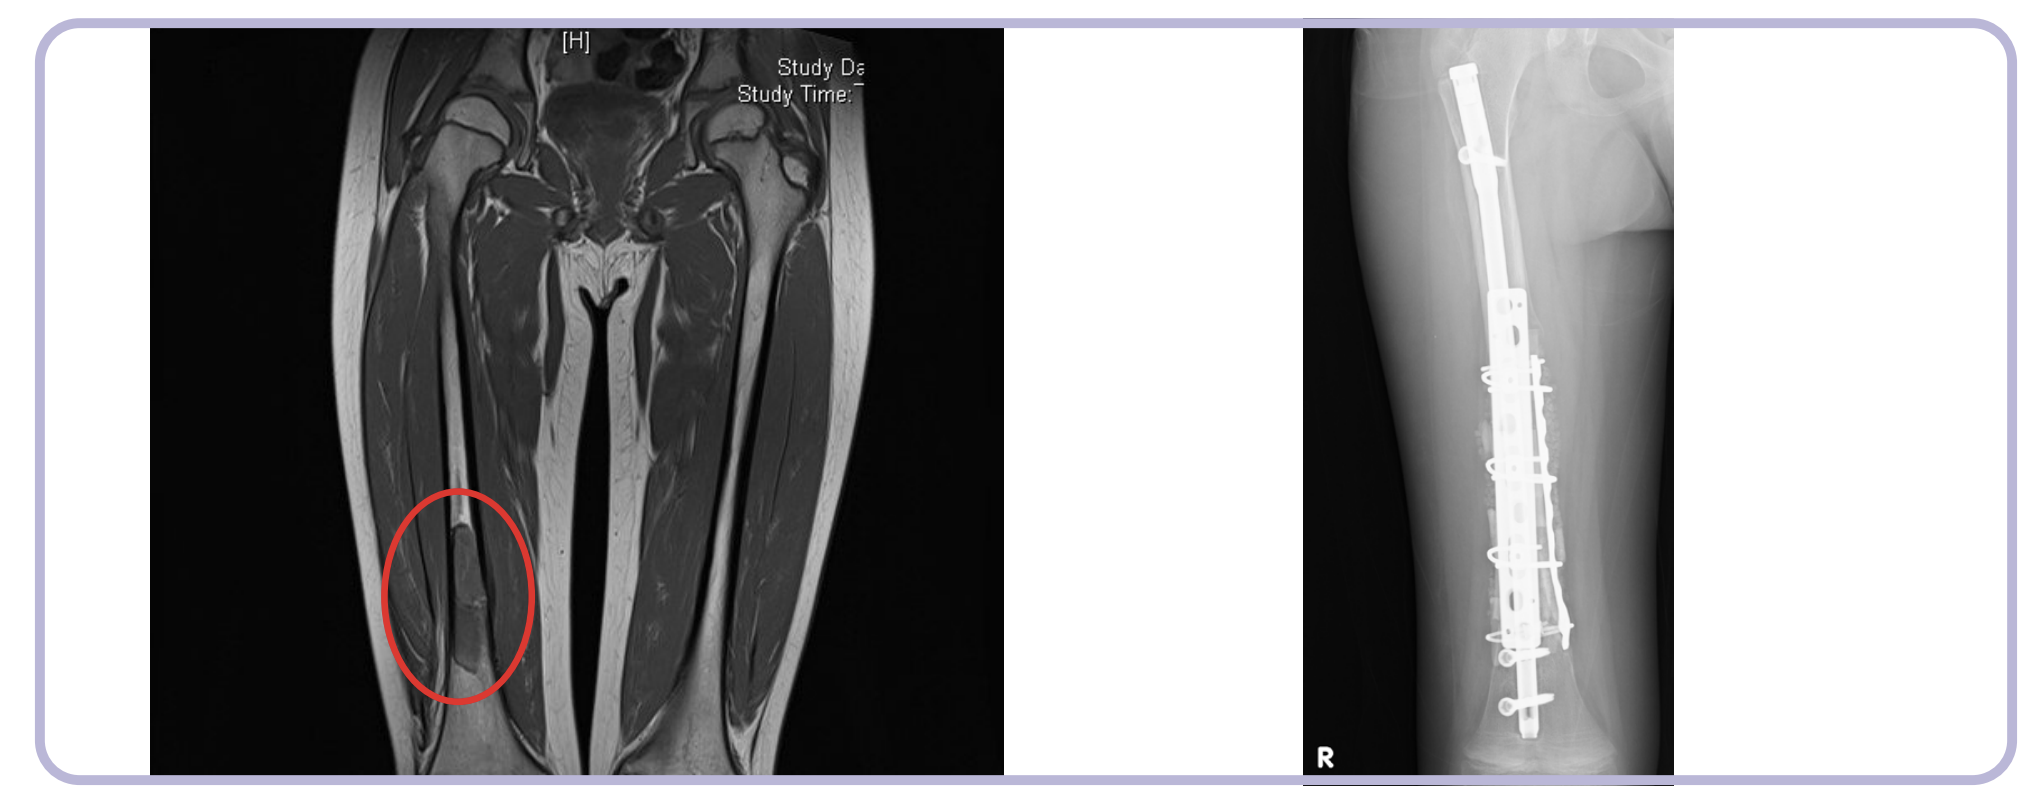

骨肿瘤切除后的“肢体保全”

在骨肉瘤或巨细胞瘤等骨肿瘤切除术中,为了保全患者肢体,往往需要切除大段骨骼。

对于良性骨肿瘤刮除后留下的巨大空腔,股骨头制成的冻干骨不仅能填充空腔,防止病理性骨折,还能提供足够的力学支撑。

创伤骨科的“急救包”

在严重车祸或高处坠落导致的粉碎性骨折中,常伴有骨质缺损。

例如在胫骨平台骨折或跟骨骨折中,关节面的塌陷需要植骨支撑。此时,库存的股骨头可以随时取用,无需额外增加手术时间去取自体骨,对于缩短危重患者的手术时间、减少出血量具有至关重要的意义。